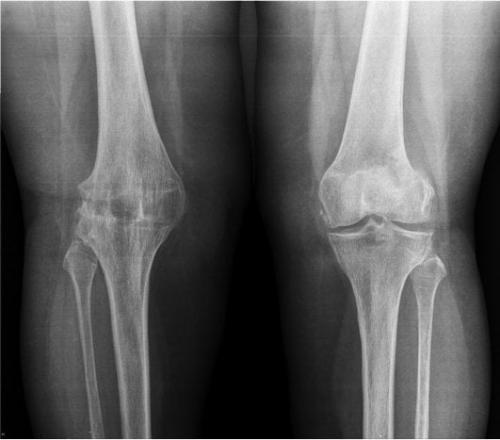

Так выглядит диагноз на рентгене.

Патологические изменения вызваны дальнейшим прогрессированием болезни, становится заметна внешняя деформация сустава и окружающих тканей, ось конечности искривлена (варусная или О-образная деформация). Клинически - хрящ сильно поврежден, истончен до 1-1,5 мм, местами видна обнаженная субхондральная кость. Костные наросты и деформация костей легко прощупываются под кожей, амплитуда движений существенно снижена. На рентгене для 3 степени характерно еще большее сужение щели. Развивается тугоподвижность в суставе с характерным хрустом, утренняя скованность, хромающая походка. Беспокоят постоянные ноющие, а иногда резкие и интенсивные боли в колене, даже в состоянии покоя. Из-за сильных болевых ощущений, пациенты часто страдают бессонницей, не могут принять удобную позу, реагируют на погодные изменения.

III стадия – клиническая картина характеризуется стойкими сгибательно– разгибательными контрактурами, резко выраженными болями и хромотой, умеренной и выраженной вальгусной или варусной деформацией конечности, нестабильностью сустава и атрофией мышц бедра и голени. При рентгенографии выявляется значительная деформация и склерозирование суставных поверхностей эпифизов с зонами субхондрального некроза и локального остеопороза, суставная щель почти полностью отсутствует, определяются обширные костные разрастания и свободные суставные тела.